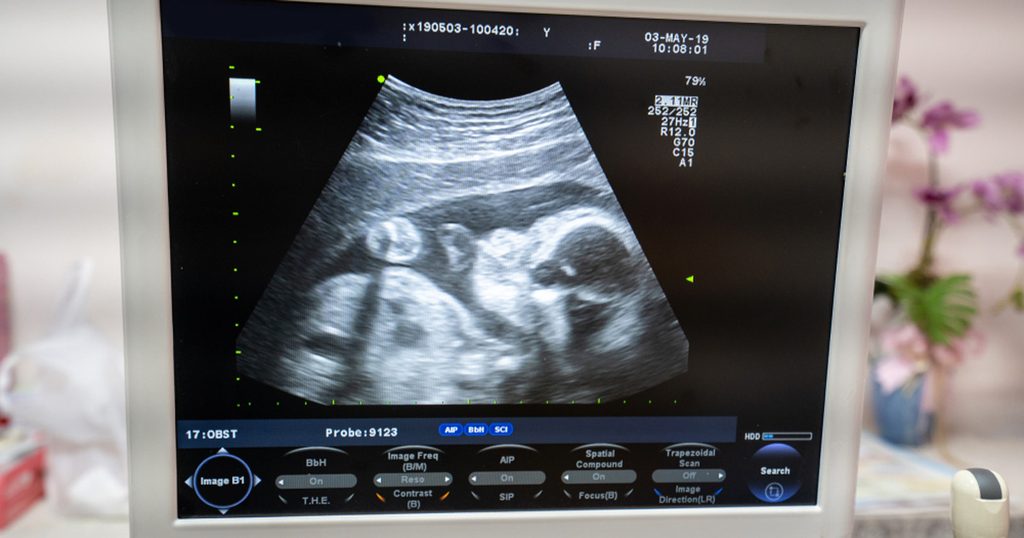

معروفٌ أن السونار هو أحد الطرق التشخيصية غير المؤلمة التي تستطيع نقل صورة ثابتة أو متحركة للأعضاء الداخلية للجسم، وتعتمد تقنية التصوير على استخدام موجات فوق صوتية عالية التردد. وفي وقت سبق أن ناقشنا فيه أهمية السونار للحامل، إليك هنا فحوصات البطن المتعلقة بالسونار.

يصدر جهاز السونار موجات فوق صوتية تمر عبر الجلد من خلال وضع محمول خاص، ثم ترتد عن الانسجة والأعضاء.

وتولد هذه الاصداء إشارات كهربائية يستطيع الكمبيوتر ترجمتها إلى صور للجزء المراد فحصه.

وقد تحصل على نتيجة أدق وصور أكثر تفصيلاً عند استبدال المحول الذي نضعه على الجلد بآخر يمكن إدخاله داخل الجسم.